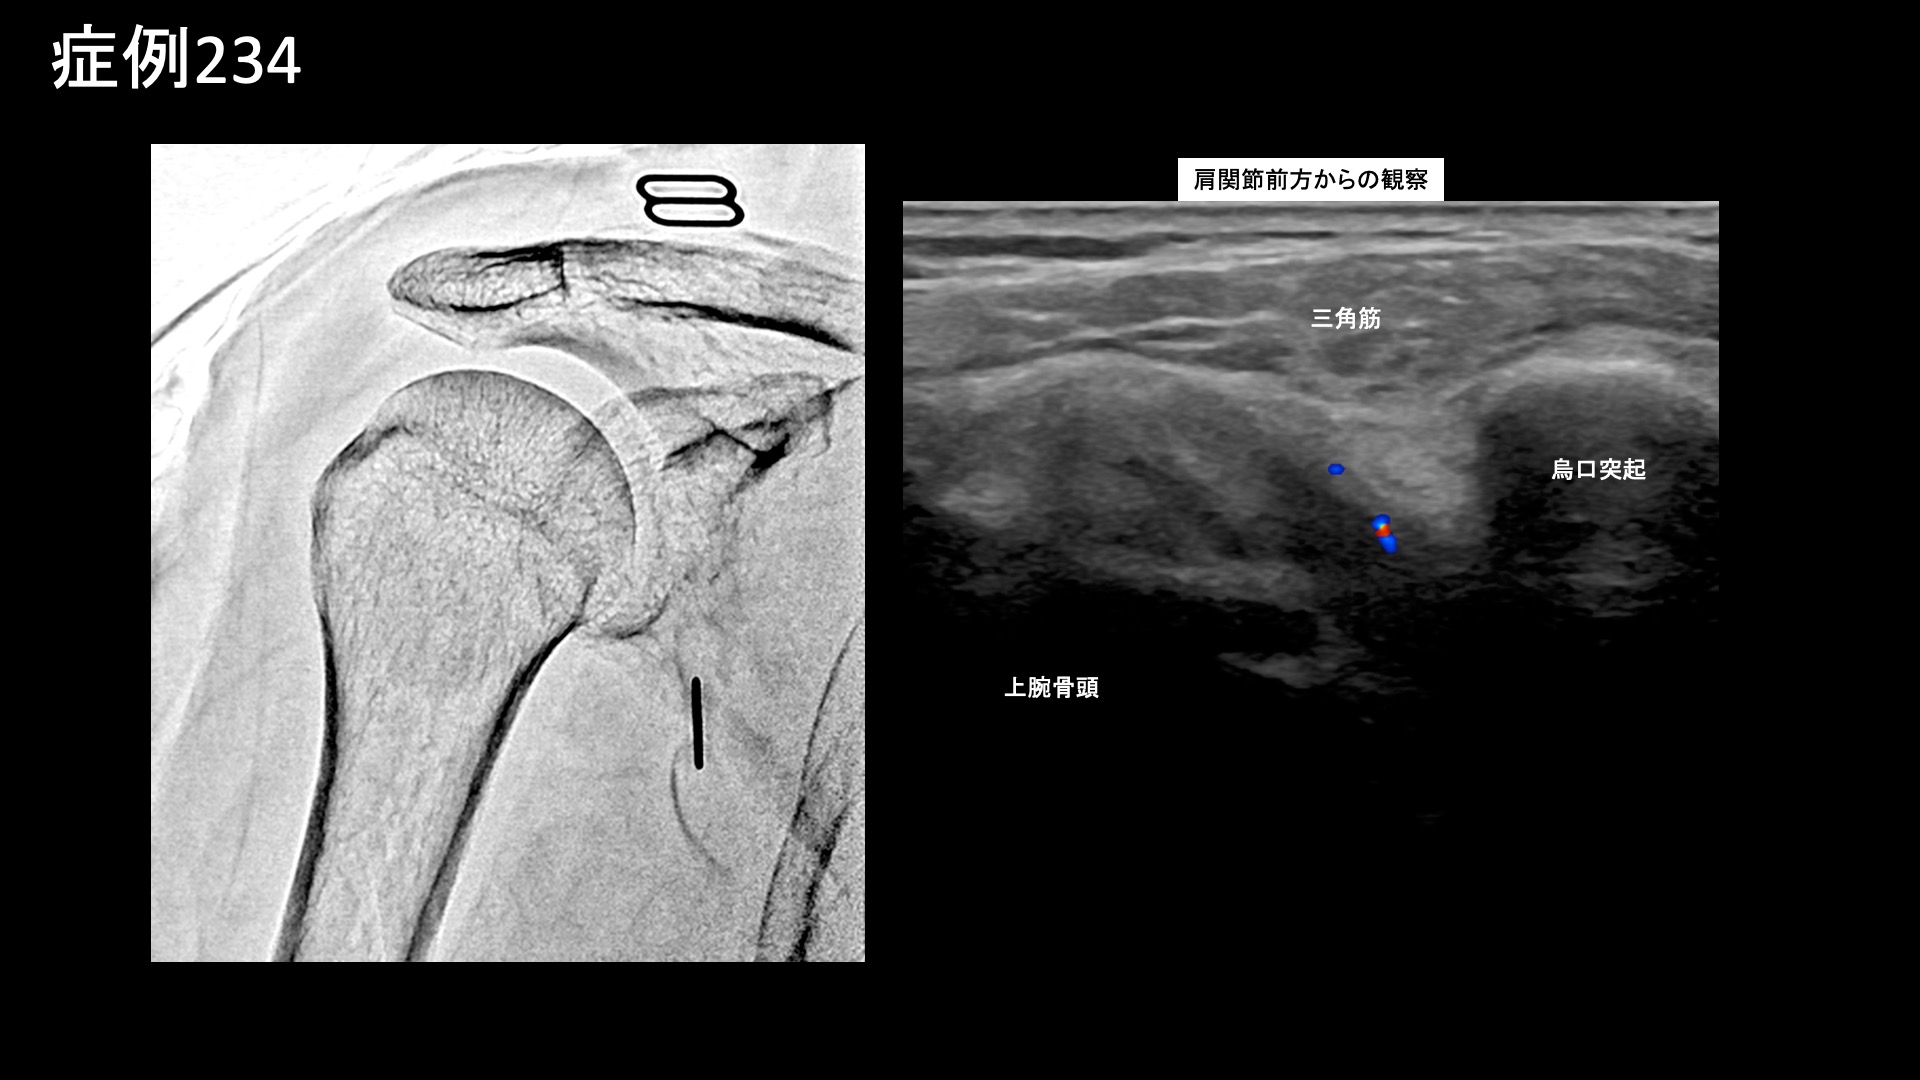

肩:肩こり・四十肩・五十肩 【50代:女性】五十肩も首肩こりも一網打尽、血管から痛みを治すカテーテル治療(五十肩、凍結肩、肩関節周囲炎、首肩こり) 2025.09.05 鴨井院長による動画解説 受診までの経過 重いものをもったことがきっかけで3ヶ月前から右肩が痛むようになりました。病院では五十肩と診断されました。ズキズキと常に痛みがあり、夜も寝られないほどでした。仰向けで寝ることはできませんでした。長年、頭痛や首肩こり(特に左側)がありましたが、それも悪化しているように感じました。 診察時の所見 右肩関節の可動域は、外転90度(真横から腕を挙げる動作で水平までが限界)、外旋45度、反対の肩に手を回すことはできず、後ろに手を回しても臀部に触れることしかできないなど、大きく制限されていました。レントゲンでは異常ありませんでしたが、エコー検査では肩関節前方からの観察において炎症に伴うモヤモヤ血管を反映した異常血流信号を認めました。腱板などの組織損傷はありませんでした。治療適応と判断し、モヤモヤ血管(病的新生血管)に対する運動器カテーテル治療(微細動脈塞栓術)を受けていただきました。 治療の所見 肩関節において血管造影を行うと、肩甲上動脈や烏口枝にてモヤモヤ血管が濃染像として描出されました。首肩こりの治療では、症状の強さに合致して、特に左深頸動脈で同様にモヤモヤ血管が描出されました。それぞれ、治療後は画像上速やかに消失しました。その他複数箇所の治療を行い終了しました。 治療後の経過 治療後2週間くらいで夜間痛がとれてきました。寝られるようにもなり、治療後1ヶ月くらいになると7割方の症状は改善し(3/10程度)、肩こりも感じなくなりました。頭痛はまだ多少ありました。痛みがとれてきたので、後は可動域だけだなと思えるようになりました。治療後2ヶ月、9割方の症状が改善し(1/10程度)、腕も上がるようになりました。外転145度まで回復していました。この間、特別なリハビリを行ったわけではありません(ほとんどの場合で不要です)。ご遠方であり、その後の受診は途絶えていますが、ここまでくればぶり返す心配はなく、残りの症状もじきに完全に消失します。五十肩はカテーテル治療によりまず間違いなく改善すると言える疾患です。頭痛や首肩こりを合併している場合は、一緒に治療可能ですので、併せてご相談いただければと思います。 五十肩の詳しい病状説明はこちら 【60代:男性】切らずに治すヘルニア治療!1ヶ月前から増悪した10年来の腰痛に対するモヤモヤ血管治療(腰椎椎間板ヘルニア、筋・筋膜性疼痛症候群) 前の記事 【60代:男性】マラソンランナーを悩ませた繰り返す肉離れによるふくらはぎの痛み(腓腹筋痛症)に対するモヤモヤ血管治療 (腓腹筋痛症、肉離れ後遺症) 次の記事